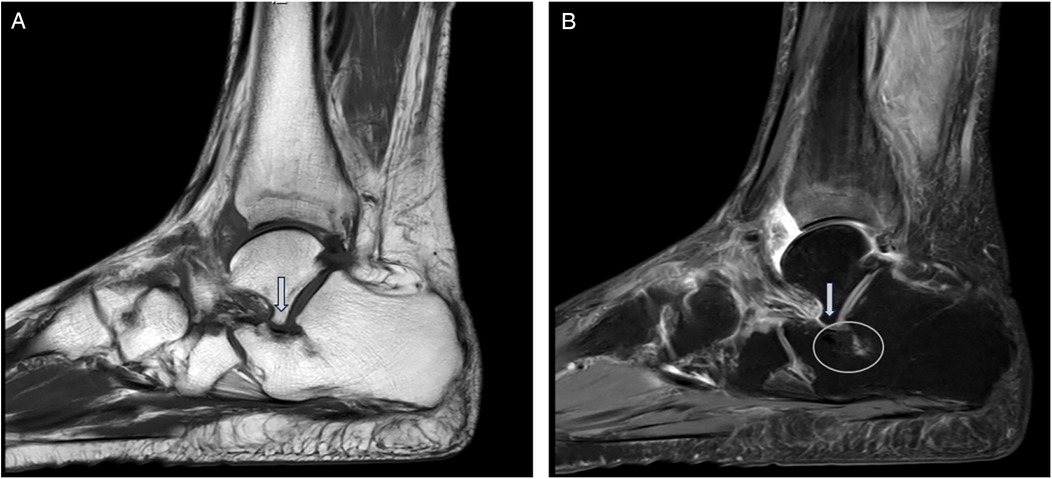

With the patient in the supine position, a tourniquet was used to prevent intraoperative bleeding after the administration of general or spinal anesthesia. The following steps were performed in all cases. Group A patients underwent arthroscopic or open resection or removal of the AALTF using an oscillating saw or osteotome, accompanied by soft tissue and bony procedures for PCFD (e.g., posterior tibial tendon debridement, flexor digitorum longus transfer, medial displacement calcaneal osteotomy, and cotton osteotomy) (Figure 2). The selection of surgical approach was mainly based on AALTF-related anatomical features: an arthroscopic approach was preferred for patients with a “significant AALTF” (maximum diameter 3–8 mm) and moderate perifacet bone marrow edema (confirmed by MRI), while an open approach was adopted for those with an AALTF larger than 8 mm, severe bone marrow edema, or a concurrent calcaneonavicular coalition to ensure complete resection of the impinging structures. The AALTF was resected to a range that allowed subtalar joint fully eversion and inversion without any impingement, confirmed under direct visualization until the entire gutter of the sinus tarsi was exposed. For patients with significant preoperative limitations in ankle dorsiflexion, either Achilles tendon lengthening or gastrocnemius recession was performed based on the results of the Silverskiold test. This procedure aimed to address soft-tissue contractures and enhance postoperative range of motion, particularly in patient with severe dorsiflexion restriction. The removal of pathologically hypertrophied synovium and fibrous tissue within the sinus tarsi was also accomplished. After completing the surgical procedure, the incision was closed and ankle stability was assessed. For group B (traditional group), only the soft-tissue or bony procedures for PCFD were performed.

Figure 2. Weight-bearing lateral x-rays of the foot before and after ankle surgery. (A) Preoperative weight-bearing lateral x-ray of the foot: the preoperative lateral view shows significant impingement between the talus and the accessory anterolateral talar facet (AALTF), with abnormal alignment. (B) Postoperative image showing improved alignment and elimination of impingement after AALTF resection and flatfoot correction surgery.